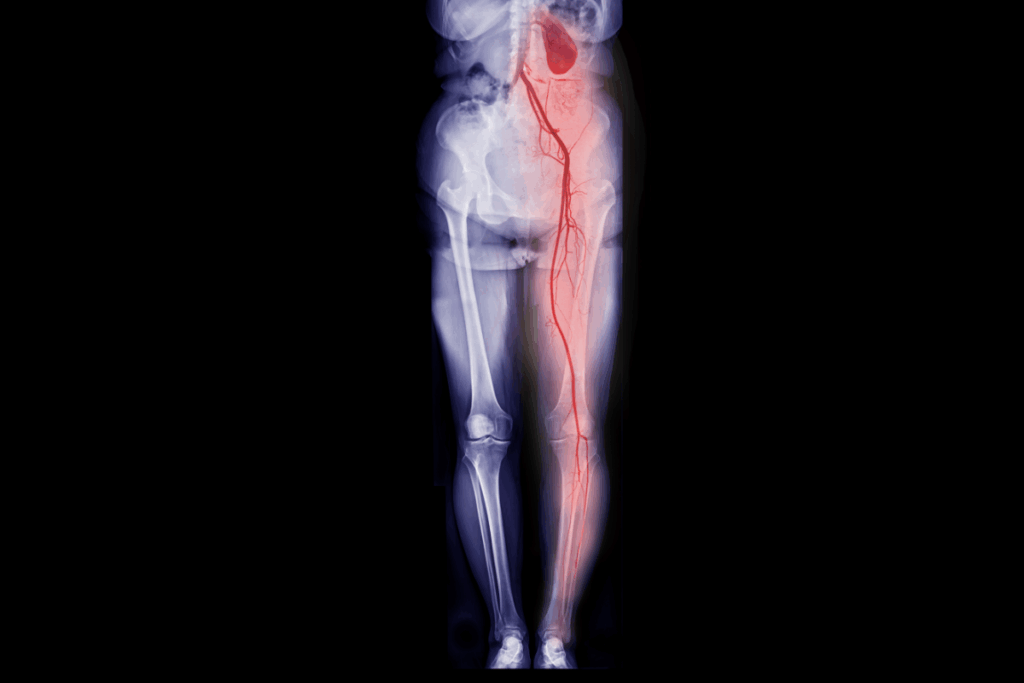

La arteriopatía periférica es una afección frecuente que limita el flujo sanguíneo a laspiernas. A menudo, se desarrolla de forma lenta, por lo que muchas personas confunden los síntomas con “cosas de la edad”. No obstante, cuando la circulación es muy deficiente, puede ocasionar una afección peligrosa llamada isquemia aguda de las extremidades, la cual es una pérdida repentina del flujo sanguíneo que requiere atención médica inmediata.

La arteriopatía periférica suele desarrollarse a lo largo del tiempo, pero, si estos síntomas aparecen de forma repentina, podría tratarse de una isquemia aguda de las extremidades, la cual es una urgencia grave en la que el tiempo es un factor importante. No espere. Solicite una revisión de inmediato.

La arteriopatía periférica no solo afecta sus piernas, sino que también afecta su independencia, comodidad y salud a largo plazo. Cuanto más pronto la detectemos, más fácil será tratarla. Mediante el diagnóstico y la atención adecuados, la mayoría de las personas pueden restablecer el flujo sanguíneo saludable, mantenerse activas y evitarcomplicaciones graves.